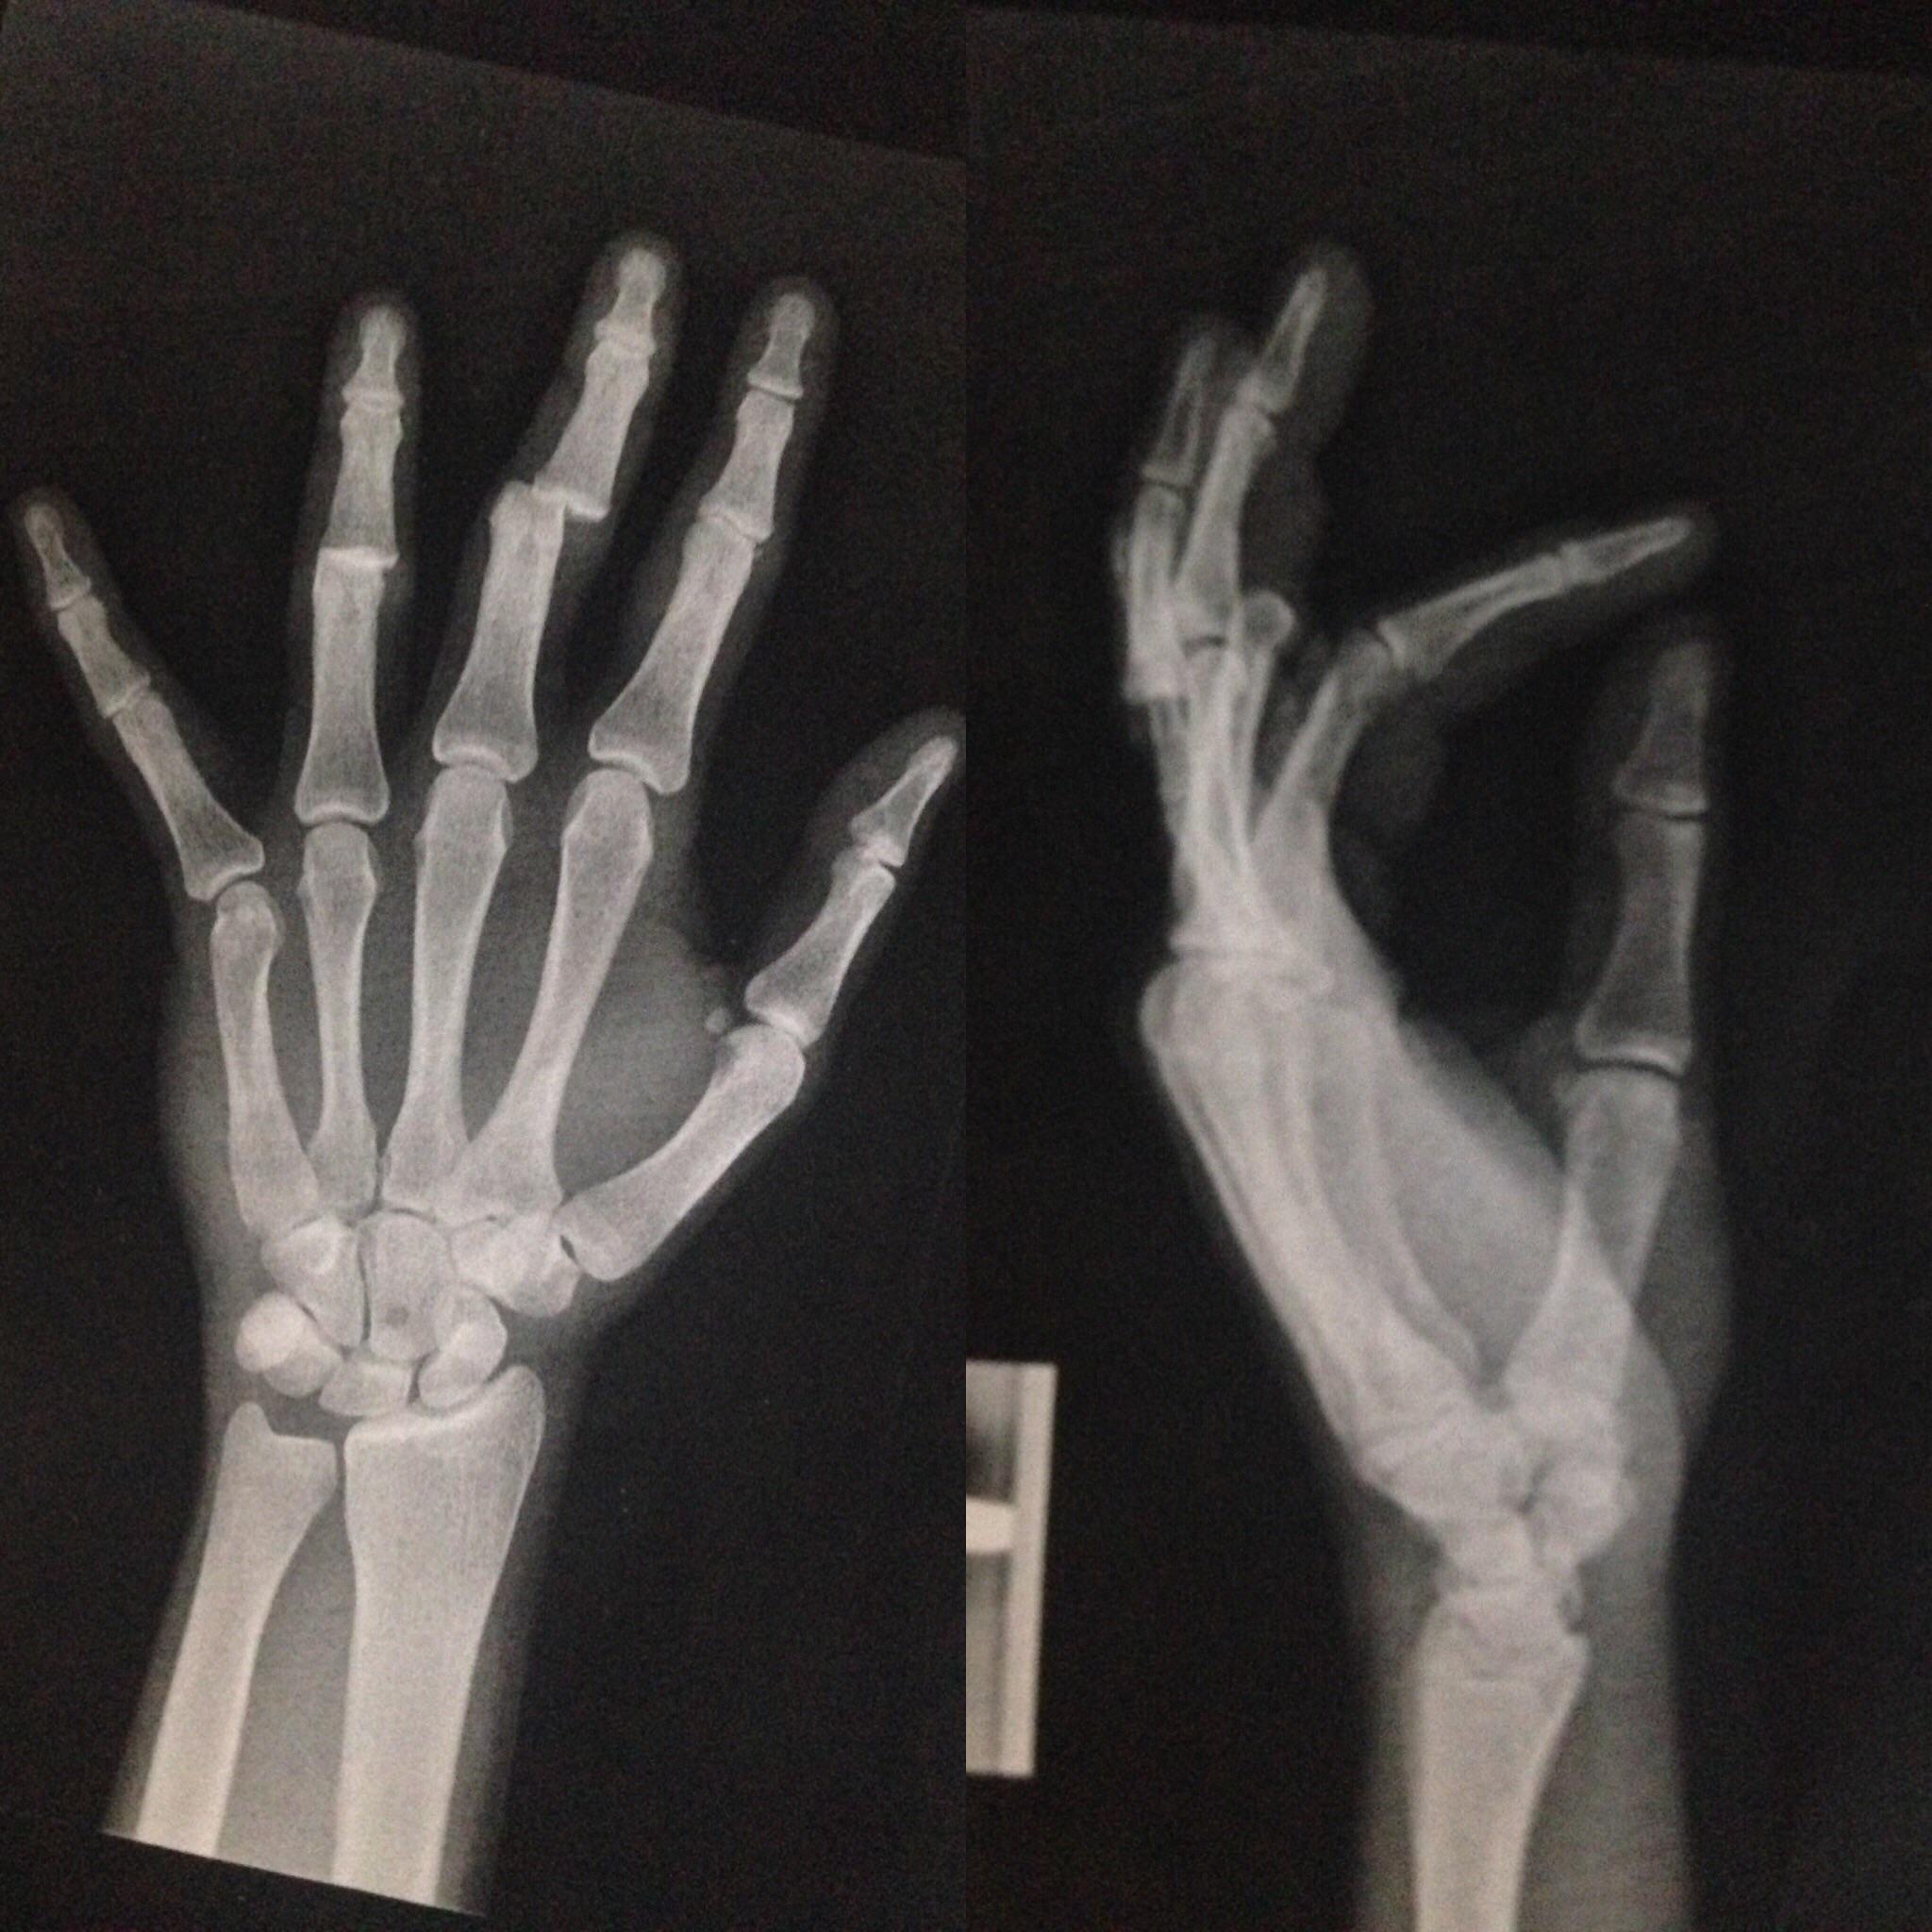

Finger X-Ray Views . Anterolateral, lateral, and oblique views of the fingers and thumb are also usually adequate to demonstrate osseous abnormalities. It is one of three views of the finger. The hand comprises the metacarpal and phalangeal bones. Finger pa view is a standard projection for radiographic assessment of the fingers; It uses a small amount of. The series examines in detail the. If the suspected abnormality is. The finger series is comprised, conventionally of a posteroanterior, oblique and a lateral view. Fractures and dislocations are usually straightforward to identify, so long as the potentially injured bone is fully visible in 2 planes.

Archive Of Unremarkable Radiological Studies Left Hand XRay Stepwards

Archive Of Unremarkable Radiological Studies Left Hand XRay Stepwards Finger X-Ray Views Fractures and dislocations are usually straightforward to identify, so long as the potentially injured bone is fully visible in 2 planes. The series examines in detail the. Anterolateral, lateral, and oblique views of the fingers and thumb are also usually adequate to demonstrate osseous abnormalities. Finger pa view is a standard projection for radiographic assessment of the fingers; The hand. Finger X-Ray Views.